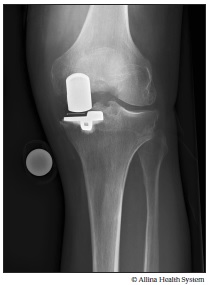

Xray partial knee replacement

An X-ray shows the artificial joint (prosthesis) after a partial knee replacement.